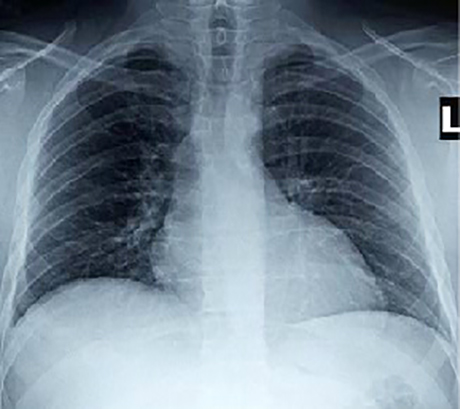

Rib Notching - PA

This chest X ray shows rib notching. In the PA view, it is demonstrated by

grooves in inferior edge of ribs.